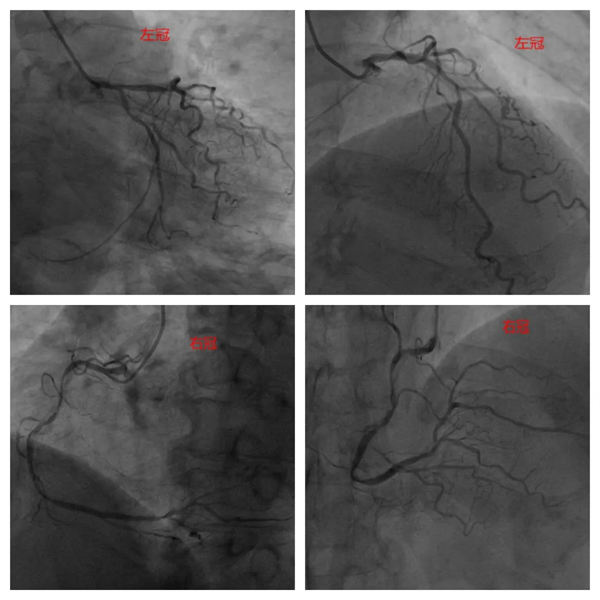

患者術(shù)前造影顯示:RCA全程彌漫性鈣化病變,近-中段狹窄70-90%,遠(yuǎn)段狹窄70%。LM鈣化狹窄50%;LAD近段鈣化狹窄60-70%,D1近段狹窄60%;LCX近段鈣化狹窄50%,遠(yuǎn)段狹窄70%。

術(shù)前造影影像